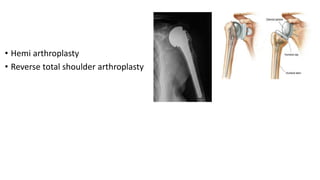

• Hemi arthroplasty

• Reverse total shoulder arthroplasty

• Hemi arthroplasty •Reverse total shoulder arthroplasty